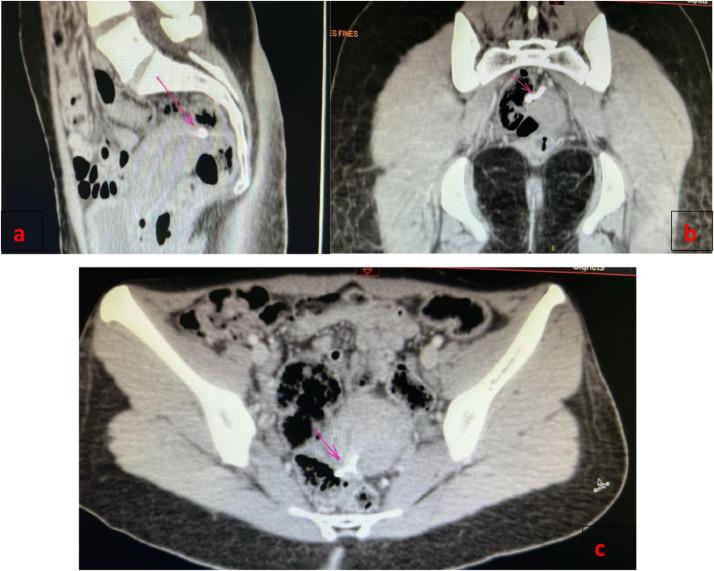

Rare case of intrauterine device rectal migration revealed by lower GI bleeding: A case report and literature review.

Rectal migration of an intrauterine device (IUD) is a rare but potentially serious complication requiring prompt diagnosis and management. We present a rare case of rectal migration of an intrauterine device (IUD) in a 26-year-old female, highlighting the clinical presentation, diagnostic evaluation, laparoscopic removal, and postoperative outcomes. This case emphasizes the critical importance of vigilant monitoring, early intervention, and close follow-up in managing IUD migration to ensure optimal patient outcomes. Timely recognition and intervention resulted in successful symptom resolution and a favorable long-term prognosis.